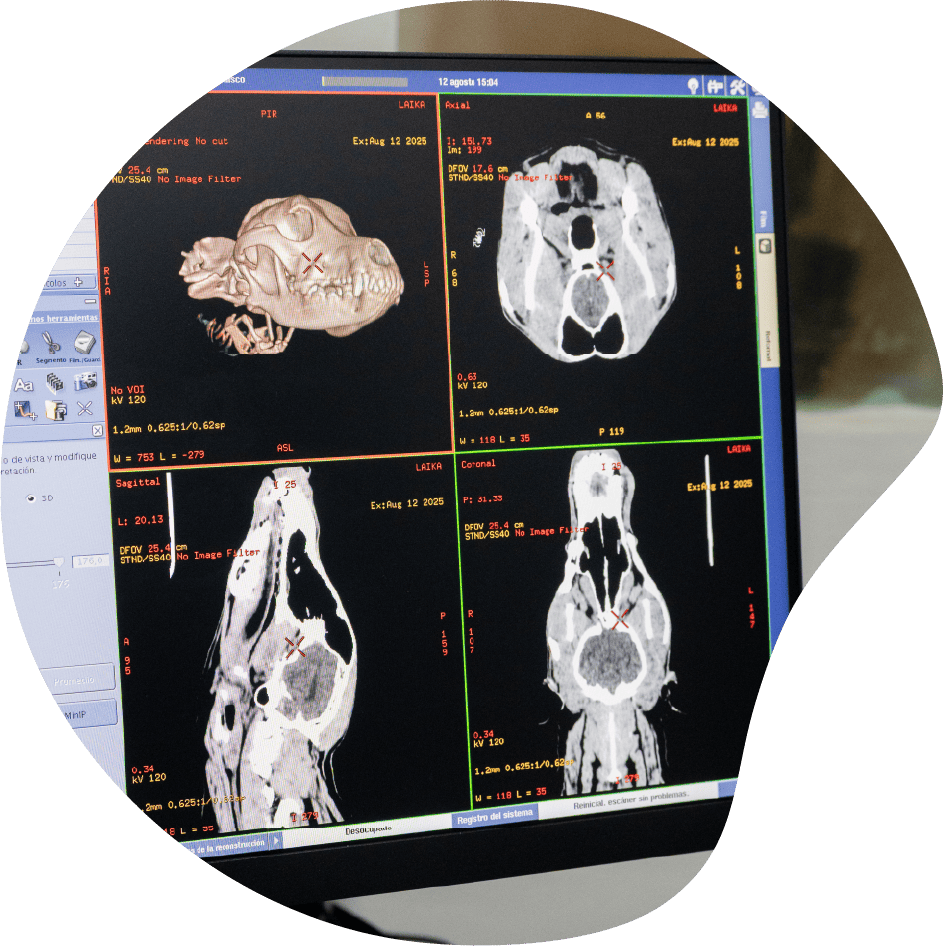

La tomografía computada (TC) es un estudio de diagnóstico por imágenes avanzado que utiliza rayos X y una computadora para generar imágenes detalladas en cortes (secciones) del cuerpo de tu mascota.

Permite ver con claridad estructuras internas que no se observan en una radiografía convencional.

Es una herramienta clave para el diagnóstico temprano y la planificación de cirugías y tratamientos complejos.